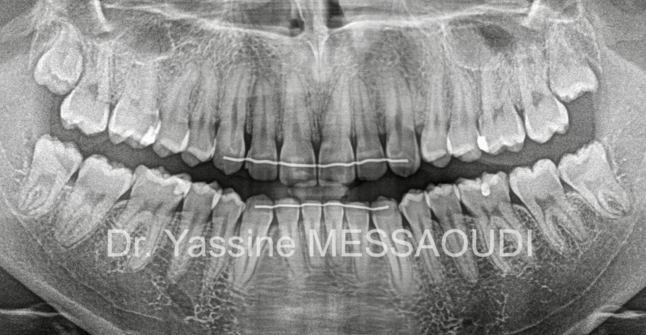

- scienceDents incluses et agénésies simples ou multiples

Traitement de canines incluses palatines bilatérales